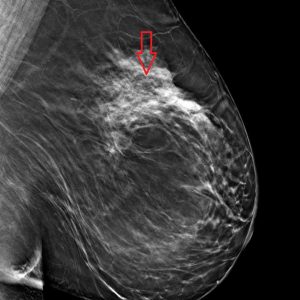

Best views of the ‘questionable distortion’ mentioned on report

- Architectural Distortion L MLO Breast Tomosynthesis

- Architectural Distortion L CC Breast Tomosynthesis